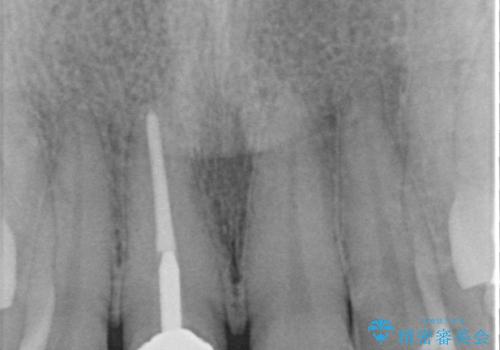

- 保険診療で装着した前歯のクラウンが変色して気になってきたとのことで来院された患者様です。

歯肉退縮による歯肉ラインの黒い縁も気になってきたとのことで、オールセラミッククラウンにて補綴治療を行うこととしました。